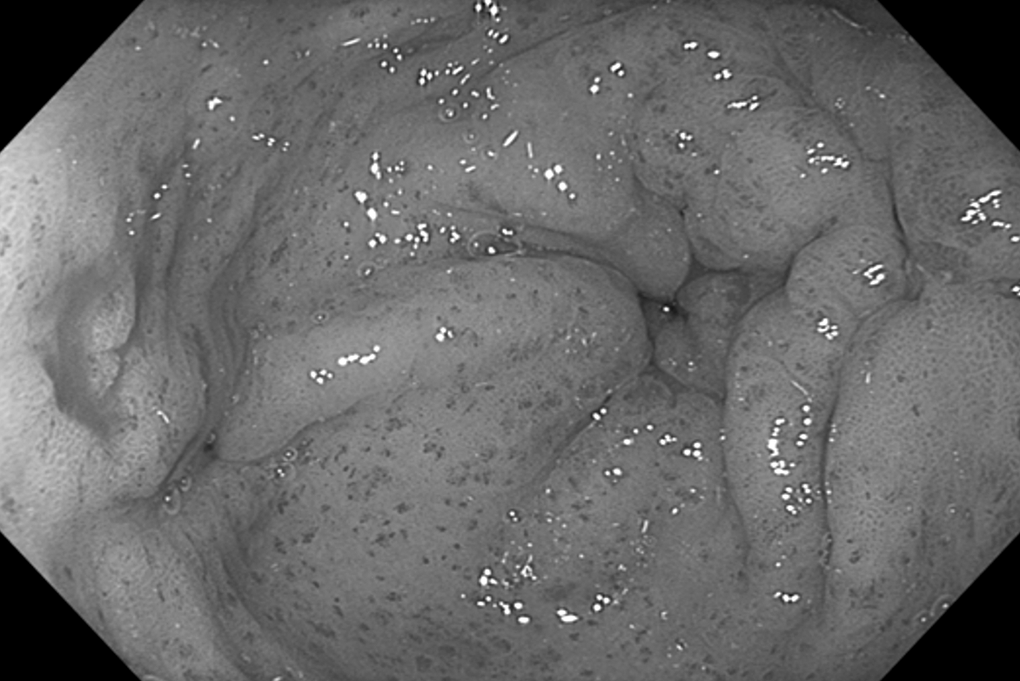

Hang vị dạ dày xuất hiện các vệt giãn mạch máu đỏ, hình ảnh đặc trưng của hội chứng “dạ dày dưa hấu” (Ảnh: BVCC).

Quá trình cấp cứu, BSCKI Nguyễn Lâm Vĩnh Phúc, Phó Trưởng khoa Nội Tổng hợp, Bệnh viện Đa khoa Quốc tế Nam Sài Gòn, phát hiện niêm mạc dạ dày người bệnh xuất hiện các vệt mạch máu giãn đỏ rực, hội tụ về phía môn vị.

Đây là hình ảnh điển hình của hội chứng GAVE (Gastric Antral Vascular Ectasia), hay còn gọi là "dạ dày dưa hấu", một nguyên nhân hiếm gặp gây xuất huyết tiêu hóa và rất dễ bị bỏ sót nếu không được nội soi kỹ lưỡng.

Do cấu trúc mỏng manh và dễ vỡ, các mạch máu này dễ gây ra tình trạng xuất huyết rỉ rả kéo dài hoặc cấp tính ồ ạt, khiến người bệnh rơi vào tình trạng thiếu máu nghiêm trọng.